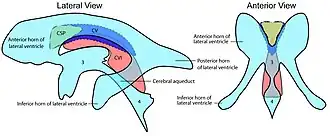

Difference between cave of septum pellucidum (CSP), cavum Vergae (CV) and cavum veli interpositi (CVI) 3 = third ventricle 4 = fourth ventricle | |

The cave of septum pellucidum is bounded anteriorly by the genu of the corpus callosum, superiorly by the body of the corpus callosum, posteriorly by the anterior limb and pillars of the fornix, inferiorly by the anterior commissure and the rostrum of the corpus callosum, and laterally by the leaflets of the septum pellucidum.[6]

In prenatal development of the fetus, the laminae of the septum pellucidum separate to form a small cavity – the cave of septum pellucidum. This is an important normal structure to identify in the sonographic assessment of the fetal brain. In post-natal life, the laminae of the septum pellucidum usually fuse, which obliterates the cavum. The cavity contains cerebrospinal fluid (CSF) that filters from the ventricles through the septal laminae.[7]

There are individual differences in the degree of CSP; whereas some have complete closure of the cavum, others present with a small degree (4–6 mm wide, in the coronal plane) of incomplete closure.[4] The most common type of CSP is noncommunicating; that is, it does not connect to the brain's ventricular system. Because of this lack of communication, the previous use of the term "fifth ventricle" is no longer used, and the fifth ventricle is the name often used for the terminal ventricle.